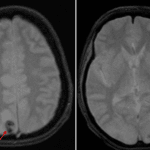

- Extensive T2/FLAIR signal hyperintensity involving the bilateral parietal and occipital lobes involving gray and white matter with associated gyral swelling and cortical restricted diffusion

- Additional areas of cortical and subcortical white matter T2/FLAIR hyperintensity involving the bilateral superior parietal lobules and posterior frontal lobes

- Multifocal areas of susceptibility artifact centered in the bilateral parietooccipital cortices

- Posterior reversible encephalopathy syndrome (PRES)

Findings are most suggestive of posterior reversible encephalopathy syndrome (PRES) involving the bilateral parietooccipital regions and to a lesser extent the bilateral posterior frontal lobes. Associated areas of developing cortical infarction with multiple small parietooccipital cortical hemorrhages. No evidence of herniation or hydrocephalus.